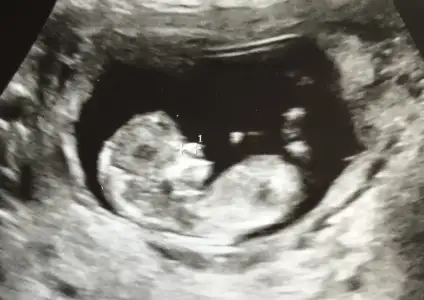

Erkek diyorumEki Görüntüle 2553261

merhaba, ben de tahmin rica edebilir miyim? 11 hafta 2 günlük bebeğim :)

Teşekkür ederim yorumunuz için :) ikra meyra’dan da tahmin alabilir miyim?Erkek diyorum

KızEki Görüntüle 2553261